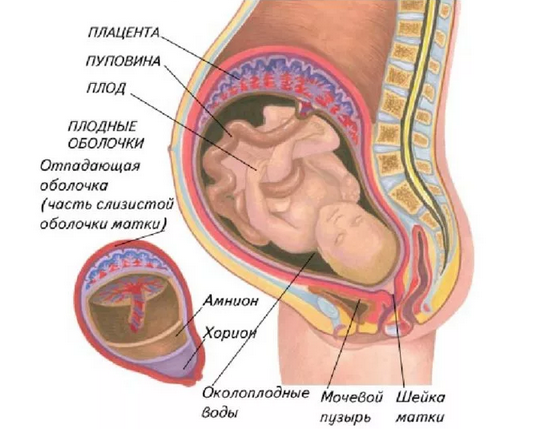

Физиология беременности: строение органов